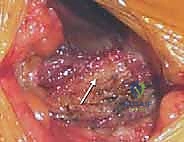

يمكن للجراح أخذ الطعم العظمي من جزأين رئيسيين في الحرقفة، ويتم اختيار الموقع بناءً على وضعية المريض أثناء الجراحة (على بطنه أم على ظهره) ونوع وكمية العظم المطلوب:

1. التشريح الأمامي لحرقفة الحوض (Anterior Iliac Crest)

يُفضل استخدام الجزء الأمامي عندما يكون المريض مستلقياً على ظهره (Supine)، وغالباً ما يُستخدم للحصول على طعم عظمي هيكلي ثلاثي القشرة (Tricortical Structural Graft)، والذي يُستخدم بكثرة في دمج الفقرات العنقية من الأمام، أو في جراحات الوجه والفكين، أو الحالات التي تتطلب دعامة هيكلية قوية لا تتحمل وزناً هائلاً.

- المعالم العظمية الرئيسية: النقطة البارزة والأكثر وضوحاً في هذه المنطقة هي الشوكة الحرقفية الأمامية العلوية (ASIS). على بعد حوالي 2 إلى 3 سنتيمترات خلف هذه الشوكة، يوجد بروز يُسمى الحديبة الحرقفية (Iliac Tubercle). هذه الحديبة هي الجزء الأكثر سمكاً واتساعاً في الحرقفة الأمامية، وتُعد الهدف الأساسي والآمن لأخذ الطعم العظمي الهيكلي.

2. التشريح الخلفي لحرقفة الحوض (Posterior Iliac Crest)

يُعد الجزء الخلفي من الحرقفة هو الموقع الأكثر شيوعاً واستخداماً لأخذ الطعوم العظمية، خاصة في جراحات دمج الفقرات القطنية والصدرية حيث يكون المريض مستلقياً على بطنه (Prone). يتميز هذا الموقع بأنه يوفر كميات هائلة من العظم الإسفنجي عالي الجودة، بالإضافة إلى إمكانية أخذ طعوم قشرية كبيرة.

- المعالم العظمية الرئيسية: النقطة البارزة هنا هي الشوكة الحرقفية الخلفية العلوية (PSIS)، والتي تظهر غالباً كغمازة أسفل الظهر فوق الأرداف. المنطقة الممتدة للأمام وللخارج من هذه الشوكة هي بنك عظمي ممتاز.